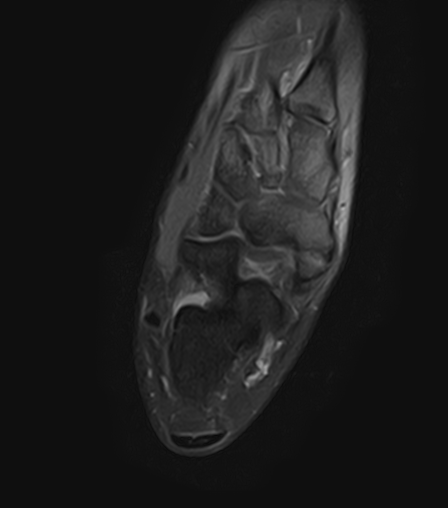

Geralmente o estudo é complementado com exames auxiliares de diagnóstico, como a radiografia dos pés em carga, onde podemos identificar o osso acessório. A ressonância magnética é de extrema importância nesta patologia para avaliar o estado tendinoso (inflamação ou rotura parcial do tendão tibial posterior) e para avaliar a presença de edema ósseo na região da sincondrose.